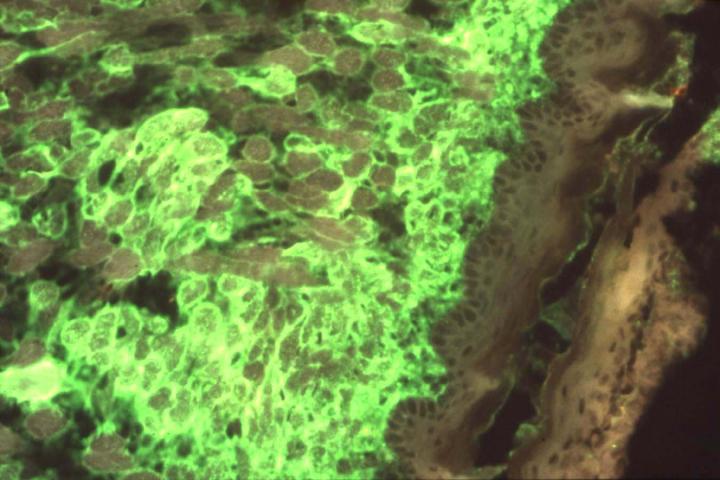

The latest DOD-funded project will seek to accelerate development of drugs and vaccines against alphaviruses, a group which comprises about 30 different viruses that are mainly transmitted by mosquitoes. This group includes eastern, western and Venezuelan equine encephalitis viruses, which are rare but very deadly and cause periodic natural outbreaks in the Americas.

"These viruses could be dangerous as bioweapons, so it is important that we work toward developing therapies against them," said Dr. Hartman, who also is research manager of the RBL. "Our goal is to better understand the biological mechanisms through which the virus harms people when it is inhaled, determine the proper timing for giving antiviral medications to people infected with the virus, and test potential therapies so that, if successful, they'll be ready for human clinical trials."